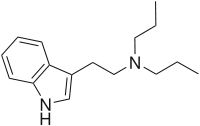

| DPT | artificial | H | CH2CH2CH3 | CH2CH2CH3 | N,N-dipropyltryptamine | 61-52-9 |